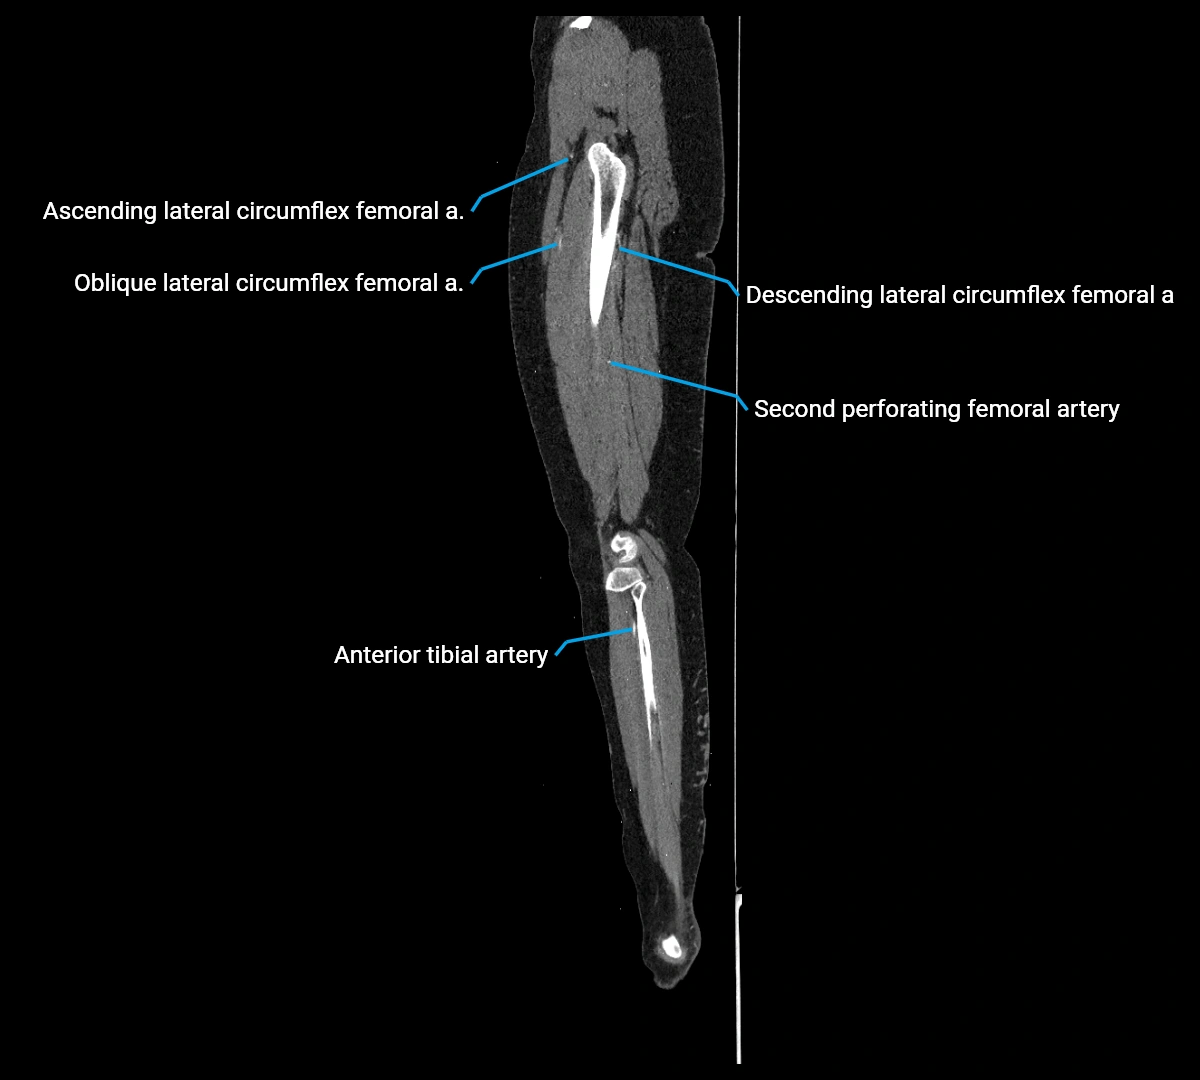

CT Appearance

Contrast-enhanced CT (CTA):

• Gold standard for abdominal aortic imaging

• Provides excellent detail of lumen, wall, aneurysm, thrombus, and branch vessels

• Multiplanar and 3D reconstructions help in aneurysm measurement, stent graft planning, and dissection evaluation

• Detects acute rupture, traumatic injury, or occlusion with high sensitivity